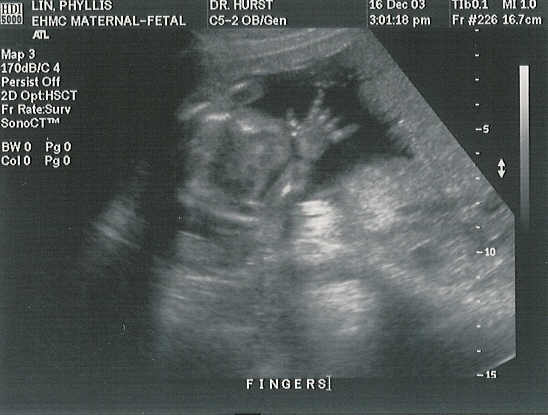

Sharka